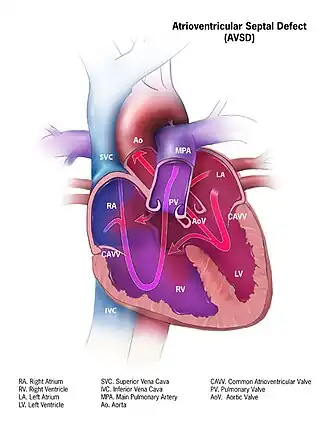

O defeito do septo atrioventricular (DSAV) ou defeito do canal atrioventricular (DCVA), também conhecido como " canal atrioventricular comum " (CAVC) ou " defeito do coxim endocárdico " (ECD), é caracterizado por uma deficiência do septo atrioventricular do coração . É causada por uma fusão anormal ou inadequada dos coxins endocárdicos superior e inferior com a porção média do septo atrial e a porção muscular do septo ventricular .

Se houver um defeito no septo, é possível que o sangue flua do lado esquerdo do coração para o lado direito do coração, ou vice-versa. Como o lado direito do coração contém sangue venoso com baixo teor de oxigênio e o lado esquerdo do coração contém sangue arterial com alto teor de oxigênio, é benéfico evitar qualquer comunicação entre os dois lados do coração e evitar o sangue dos dois lados do coração de se misturarem.[8]

- No AVSD parcial, há um defeito na parte primum ou inferior do septo atrial, mas nenhuma comunicação intraventricular direta ( defeito do ostium primum ).

- No AVSD completo (CAVSD), há um grande componente ventricular abaixo de um ou ambos os folhetos de ponte superior ou inferior da válvula AV. O defeito envolve toda a área de junção das câmaras superior e inferior do coração, ou seja, onde os átrios se unem aos ventrículos. Há um grande orifício entre a porção inferior dos átrios e a porção superior ou "de entrada" dos ventrículos e isso está associado a uma anormalidade significativa das válvulas que separam os átrios dos ventrículos. As válvulas de fato tornam-se uma válvula atrioventricular comum, e a gravidade do defeito depende em grande parte das ligações de suporte da válvula aos ventrículos e se a válvula permite fluxo dominante do átrio direito para o ventrículo direito e do átrio esquerdo para o esquerdo ventrículo (fluxo "desequilibrado"). Os problemas gerais são semelhantes aos do VSD, mas são mais complicados. Há um aumento do fluxo sanguíneo para os pulmões através dos componentes ventricular e atrial do defeito. Além disso, a válvula atrioventricular anormal invariavelmente vaza, de modo que, quando os ventrículos se contraem, o sangue flui não apenas para o corpo e os pulmões, mas também para os átrios. O efeito da contrapressão nos átrios causa congestão de sangue no átrio esquerdo em particular, e isso por sua vez causa congestão nas veias que drenam os pulmões. O efeito no bebê é piorar a insuficiência cardíaca associada a uma CIV isolada e acelerar o aparecimento de hipertensão pulmonar. Deve-se mencionar que o CAVSD é encontrado em aproximadamente um terço dos bebês com síndrome de Down, mas também ocorre como uma anormalidade isolada.